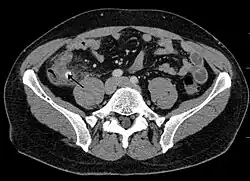

A CT scan demonstrating acute appendicitis (note the appendix has a diameter of 17.1 mm and there is surrounding fat stranding).

Where it is readily available, computed tomography (CT) has become frequently used, especially in people whose diagnosis is not obvious on history and physical examination. Although some concerns about interpretation are identified, a 2019 Cochrane review found that the sensitivity and specificity of CT for the diagnosis of acute appendicitis in adults was high.[63] Concerns about radiation tend to limit use of CT in pregnant women and in children, especially with the increasingly widespread usage of MRI.[64][65]

The accurate diagnosis of appendicitis is multi-tiered, with the size of the appendix having the strongest positive predictive value, while indirect features can either increase or decrease sensitivity and specificity. A size of over 6 mm is both 95% sensitive and specific for appendicitis.[66]

However, because the appendix can be filled with fecal material, causing intraluminal distention, this criterion has shown limited utility in more recent meta-analyses.[67] This is as opposed to ultrasound, in which the wall of the appendix can be more easily distinguished from intraluminal feces. In such scenarios, ancillary features such as increased wall enhancement as compared to adjacent bowel and inflammation of the surrounding fat, or fat stranding, can be supportive of the diagnosis. However, their absence does not preclude it. In severe cases with perforation, an adjacent phlegmon or abscess can be seen. Dense fluid layering in the pelvis can also result, related to either pus or enteric spillage. When patients are thin or younger, the relative absence of fat can make the appendix and surrounding fat stranding difficult to see.[67]